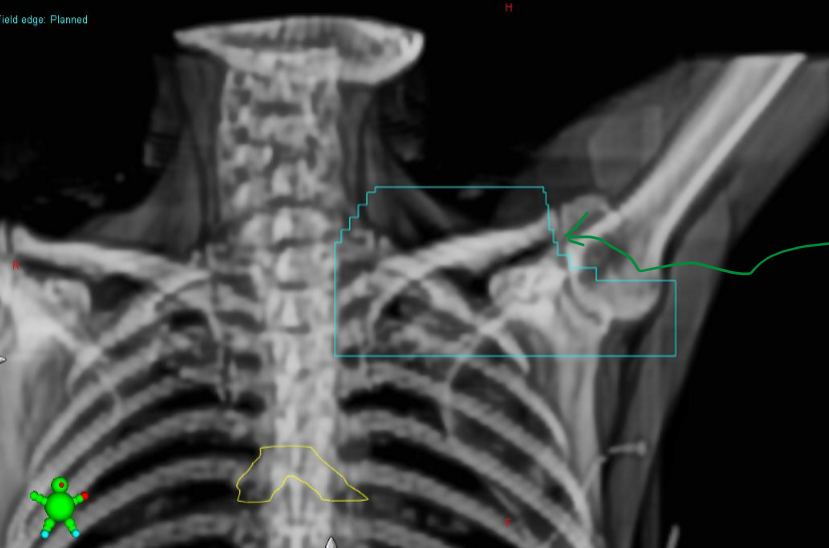

what set of images are done for field localization in breast treatments?

orthogonal reference images: often ANT and LAT images

what does the wire define on the x-ray imaging?

wire defines the surgical scar

what are the yellow contours on the image?

contours placed by dosimetry to mark the site of surgical clips

What are the primary and secondary match structures for Sup/Inf for breast treatments

primary = clavicle head - sternoclavicular joint region

secondary = intervertebral spaces, apex of lung, ribs, carina

what may be used in conjunction with the clavicle head to get match exact?

the intervertebral spaces

what are the lateral primary and secondary match structures for breast treatments

primary = thoracic vertebrae (lateral edge or spinous processes)

secondary = rib cage / heart shadow

how much of the thoracic vertebrae should be used when doing lateral match and why?

use as much of thoracic spine as possible as the target volume is quite long

what are the Ant / Post primary and secondary match structures for breast treatments

primary = sternum (especially for DIBH techniques): manubrium / sternal body or anterior edge of thoracic vertebrae

seconday = anterior edge of thoracic vertebrae or sternum (whatever you didn’t use as primary, use as secondary)

why is the contoured carina added on to the DRR

because the carina is not well visualized without it